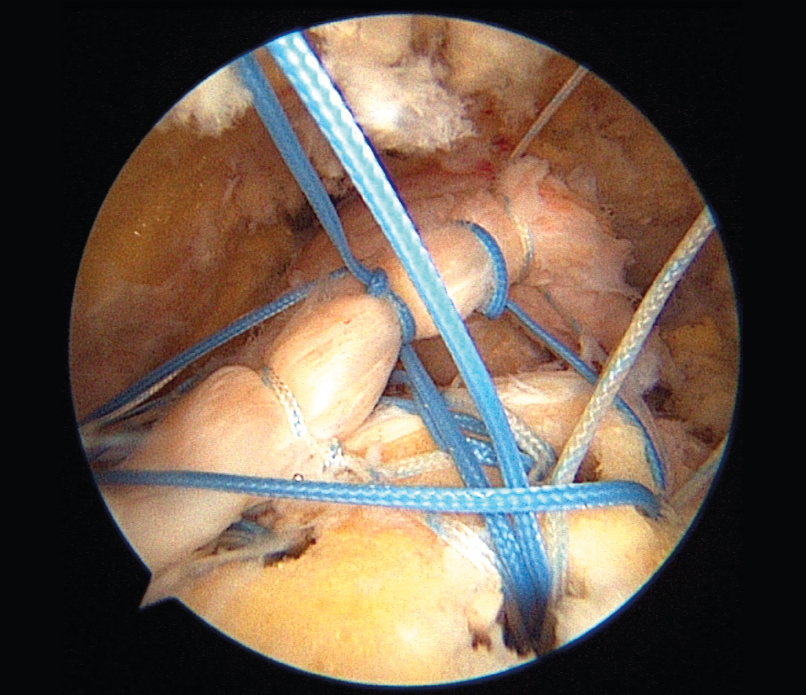

El manejo de las lesiones del manguito rotador con técnica de “doble hilera” ha permitido mejorar la biomecánica de la reparación tendinosa mejor que las técnicas previamente utilizadas. Además, permite maximizar el área de contacto de la reparación. También los estudios de metaanálisis realizados han demostrado mejores resultados de las escalas funcionales y de integridad de los tendones reparados respecto a la técnica de “hilera simple”. En esta fotografía se observa el diseño, previo a su reducción y fijación, de una reparación de manguito rotador en un hombro derecho con visión lateral y reconstrucción por técnica de “doble hilera”.